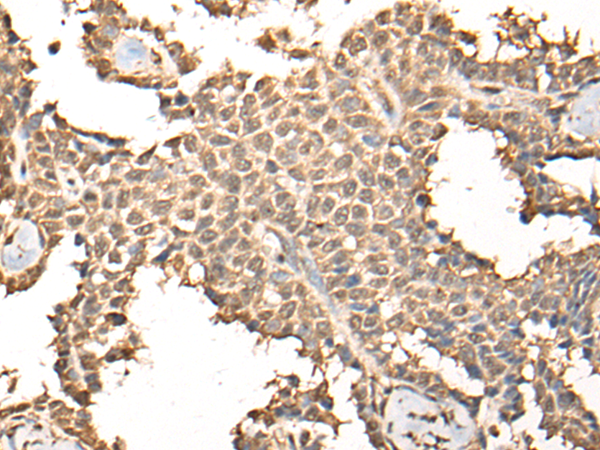

IHC positive control: |

Human ovarian cancer and human thyroid cancer |